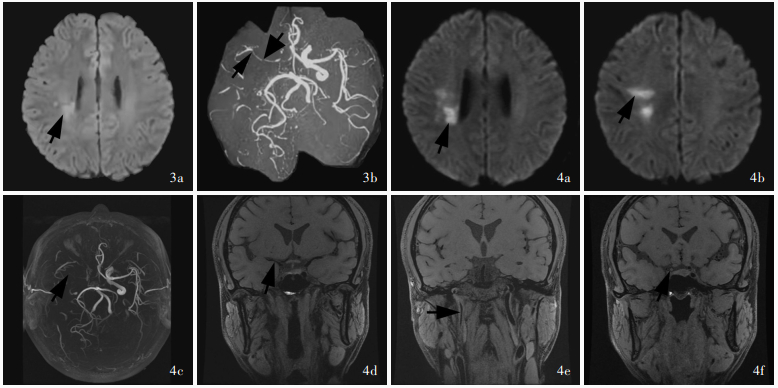

Sugiyama A , Yokota H , Misawa S , Mukai H , Sekiguchi Y , Koide K , Suichi T , Matsushima J , Kishimoto T , Tanei ZI , Saito Y , Ito S , Kuwabara S . Cerebral large artery stenosis and occlusion in POEMS syndrome. BMC Neurol, 2021, 21: 239.

doi: 10.1186/s12883-021-02260-2

Takahashi Y , Mochizuki Y , Nakamura K , Katoh N , Sekijima Y . Moyamoya disease-like cerebrovascular stenotic lesions are an important phenotype of POEMS syndrome-associated vasculopathy. Intern Med, 2022, 61: 1603- 1608.

doi: 10.2169/internalmedicine.7701-21

Sodavarapu S , Mahajan A . Ischemic stroke in a patient with polyneuropathy, organomegaly, endocrinopathy, monoclonal protein, and skin changes syndrome treated with lenalidomide. Cureus, 2020, 12: e9346.

Kubota Y , Hanaoka Y , Koyama JI , Takahashi Y , Katoh N , Iwaya M , Fujii Y , Ogiwara T , Horiuchi T . Surgical revascularization for quasi-moyamoya disease associated with polyneuropathy, organomegaly, endocrinopathy, monoclonal gammopathy, and skin changes (POEMS) syndrome: a case report and literature review. Nagoya J Med Sci, 2023, 85: 141- 149.